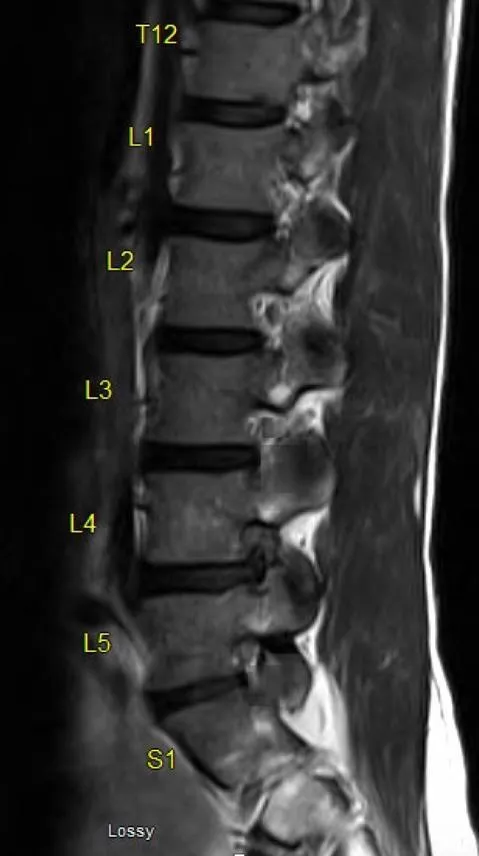

Lumbar Degeneration - Low Back Breakdown

- Core Issues: Age-related wear & tear of lumbar discs, facets, ligaments. Leads to Low Back Pain (LBP), radiculopathy (e.g., sciatica), and/or neurogenic claudication.

- Disc Herniation: Nucleus pulposus extrusion. Common at L4-L5, L5-S1. Positive Straight Leg Raise (SLR).

- Lumbar Spinal Stenosis (LSS): Central canal or foraminal narrowing.

- Degenerative Spondylolisthesis: Anterior vertebral slippage, often L4-L5.

- Diagnosis: History, neuro exam. X-ray (osteophytes, ↓disc height). MRI is gold standard.

⭐ The "shopping cart sign" (symptoms improve with leaning forward) is characteristic of lumbar spinal stenosis.

- Lumbar spondylosis is most common, affecting L4-L5 & L5-S1 levels.

- Degenerative spondylolisthesis commonly occurs at L4-L5.